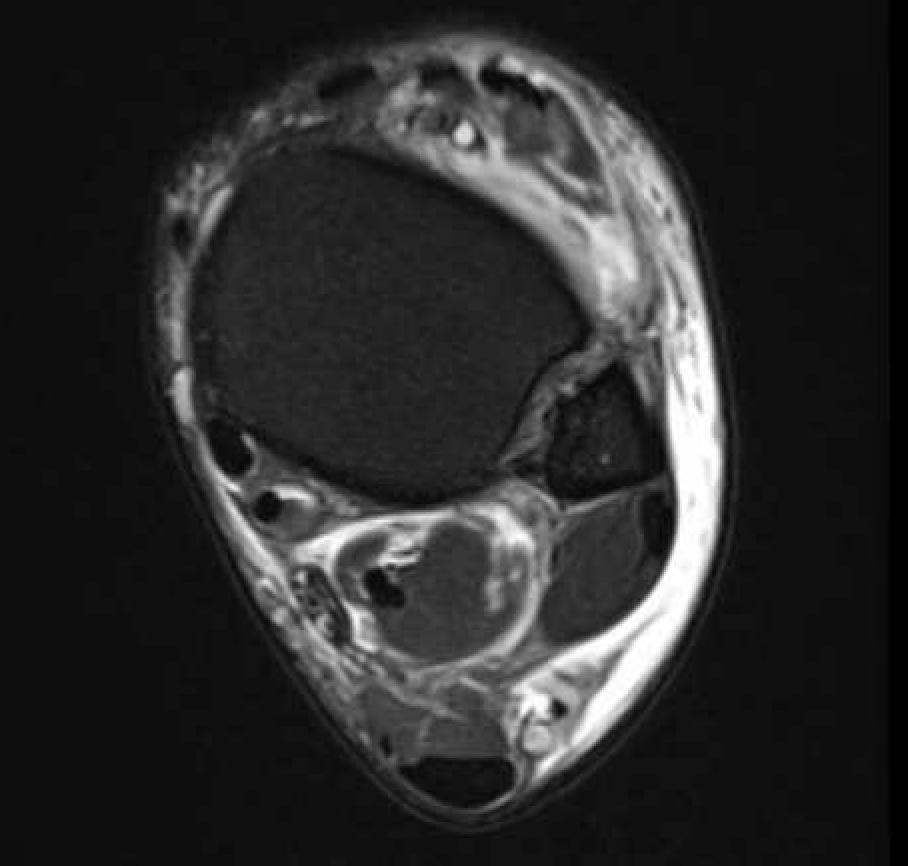

MRI

Normal anatomy

Tear of AITFL / intact PITFL

Tear of AITFL, intact PITFL, and syndesmotic injury with external rotation of the fibula

Tear of AITFL & PITFL with syndesmotic widening